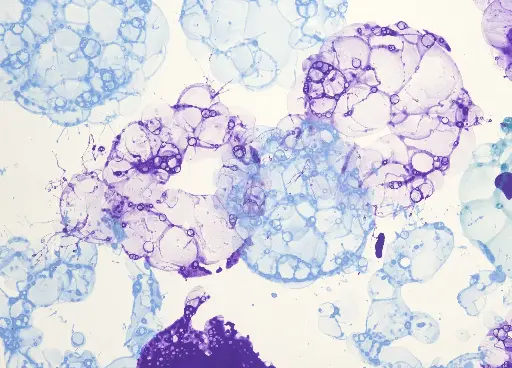

Peutz-Jeghers Syndrome: From Genetic Mutation to Cancer Prevention

This comprehensive course provides an in-depth understanding of Peutz-Jeghers Syndrome (PJS), a rare hereditary condition characterized by gastrointestinal polyps and distinctive mucocutaneous pigmentation. Learners will explore the clinical presentation, diagnostic methods, genetic basis, associated cancer risks, and management strategies. Designed for medical students, healthcare professionals, and researchers, this course also covers modern guidelines for surveillance and family counseling.